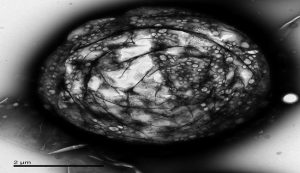

İsveç ve Finlandiya ortaklığında yürütülen bir çalışma sonucunda, insan hücrelerinin DNA’sındaki “beşinci baz” diye de söz edilen “metillenmiş sitozin“in, genetik